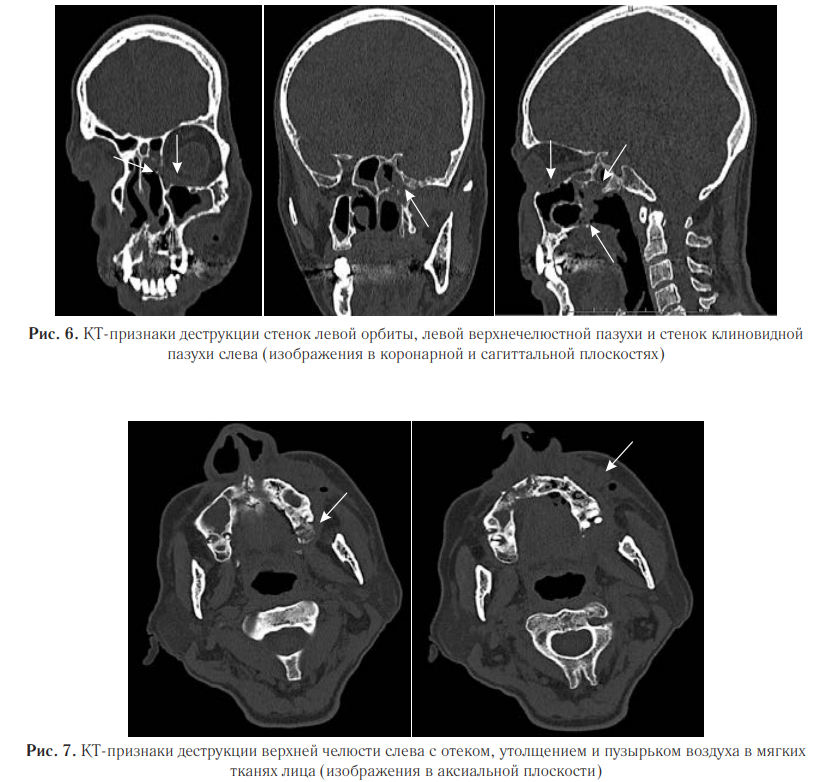

На реконструкции КТ-изображений в коронарной и сагиттальной плоскостях выявили деструкцию и истончение медиальной, нижней стенок левой орбиты, задней стенки левой верхнечелюстной пазухи, боковой и нижней стенки основной пазухи слева (рис. 6).

Также были выявлены деструктивные изменения верхней челюсти с утолщением и эмфиземой мягких тканей лицевой области слева (рис. 7). Пациент был переведен в специализированное отделение. Проведена секвестрэктомия верхней челюсти, удаление зубов слева. В гистологических препаратах послеоперационного материала выявлены нити мицелия. При пересмотре гистологического материала в НИИ Медицинской микологии им. П. Н. Кашкина, был обнаружен широкий несептированный мицелий, характерный для мукоромицетов. На основании клинической картины, данных КТ и микологического обследования был диагностирован COVID-ассоциированный мукормикоз околоносовых пазух и структур орбиты. Назначили антимикотическую терапию: введение липосомального амфотерицина В 10 мг/кг в сутки, после стабилизации состояния переход на пероральную терапию. По месту ведения пациента была начата антимикотическая терапия липидным амфотерицином В 14 дней, далее амфотерицином В дезоксихолатом, который был отменен ввиду нефротоксичности. В последующем лечение продолжили изавуконазолом в стандартной дозе. Согласно международным рекомендациям, проводился контроль уровня глюкозы крови и произведена отмена ГКС. Общая продолжительность лечения составила 105 дней. Ежедневно в первую неделю, затем по мере необходимости проводили осмотр области оперативного вмешательства с местной обработкой слизистых оболочек препаратами амфотерицина В. После проведенной антимикотической терапии на контрольных МСКТ ОНП выявили признаки стабилизации мукормикоза в виде отсутствия прогрессирования процесса; склерозирования, утолщения и гиперостоза костей; уменьшения отека и утолщения мягких тканей с их фиброзированием (рис. 8, 9).